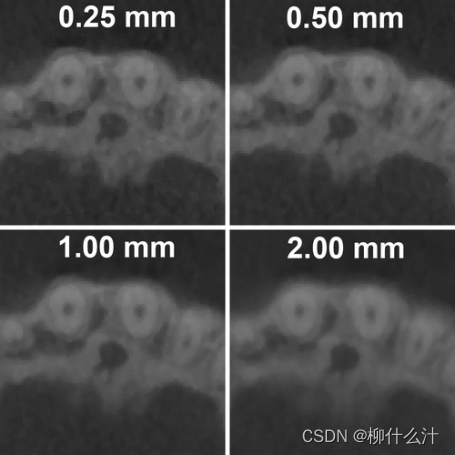

在重建过程中,也可以应用基本的滤波,以使图像平滑或锐化。另外可以通过增加切片厚度使图像变得平滑。通过对多个连续的切片进行平均加厚,可以减少图像的噪声,但是要牺牲图像的清晰度,可以建议,当需要观察小的细节是,不应大大增加切片厚度。注意,切片厚度不应该与切片间隔想混淆,后者改变了切片的数量,但不会改变一个切片内的图像质量。为了限制数据的大小,在输出CBCT图像之前通常会增加切片间隔。由于切片之间的信息缺失,在执行时应有所估计,尽管这可以通过在导出轴线图像的同时同时到处冠状和矢状堆叠来部分弥补。切片厚度和切片间隔通常时同时选择的。当观察小的细节时,切片厚度和切片间隔的值应尽可能小(例如,与体素大小相同)。

增加切片厚度可以减少清晰度和噪音。图像的体素大小为0.25毫米。为了说明问题,所有图像都被放大到800%。